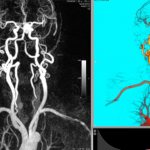

Обычно оно включает МРТ, УЗИ сосудов головы и шеи, офтальмоскопию и консультацию у узких специалистов. После этого специалист сможет определить истинный диагноз, который и будет определять дальнейшую тактику лечения.